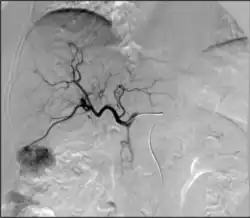

• Embolization: Placement of a metallic coil or embolic substance (gel-foam, poly-vinyl alcohol) to block blood through to a blood vessel, either to stop bleeding or decrease blood flow to a target organ or tissue.[7]

• Chemoembolization: Combined injection of chemotherapy and embolic agents into the arterial blood supply of a tumor, with the goal of both local administration of chemotherapy, slowing "washout" of the chemotherapy drug, and also decreasing tumor arterial supply

• Radioembolization: Combined injection of radioactive glass or plastic beads and embolic agents into the arterial blood supply of a tumor, with the goal of both local administration of radiotherapy, slowing "washout" of the radioactive substance, and also decreasing tumor arterial supply

• Transarterial embolization (TAE)/bland embolization: Injection of embolic material (microparticles, alcohol, glue) through a catheter into the arteries feeding a tumor to completely occlude the tumor's blood supply and cause cell death. The most common indication is for treatment of unresectable liver cancer (hepatocellular carcinoma).[64]

• Transarterial chemoembolization (TACE): Injection of a chemotherapy agent often with microparticles through a catheter into arteries feeding a tumor that both delivers chemotherapy and blocks the blood supply to the tumor to cause cell death[65]